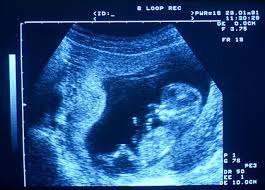

Pour une grossesse épanouie,

une prévention primaire et un dépistage précis.

Nos interventions chirurgicales et médicales couvrent la santé de la femme tout au long de sa vie (gynécologie) ainsi que le suivi de la grossesse, l'accouchement et le post-partum (obstétrique). Notre cabinet prend en charge la fertilité, la ménopause, la chirurgie pelvienne/mammaire et le dépistage oncologique.